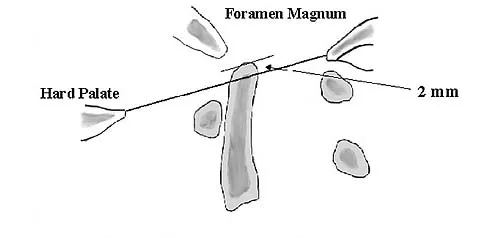

Question 25

A 25-year-old man has chronic back pain that has been slowly worsening. He has no constitutional symptoms, and he denies any previous medical problems. Examination shows a tall lean build with no objective neurologic findings or skin lesions. Figure 32 shows a T2-weighted sagittal MRI scan. What is the most likely diagnosis?

Explanation